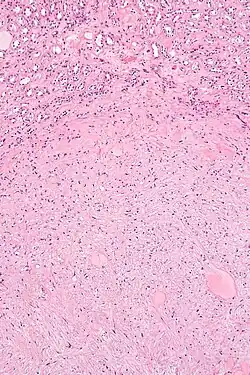

| Micrograph of a renal medullary fibroma (bottom of image). Renal tubules are seen at the top of the image. H&E stain. | |

They consist of bland spindle-shaped or stellate-shaped cells in a loose stroma. Renal tubules may be entrapped.

High mag.